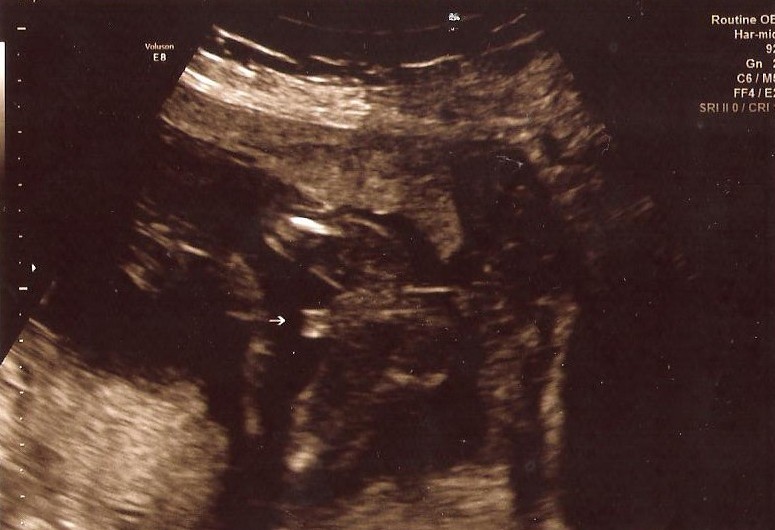

This is my little peanut at 18 weeksAttachment 21739

Baby boy. An circular object can image as 3 lines on an ultrasound.

This is not the typical 3 lines you're looking for in a girl

Possibly swollen girl parts

Id lean boy. Did they give you any other shots?

Looks too big amd sticking out too much to be a girl. I think boy.

Thank you ladies, for helping me out! This is the only pic tech gave me! She said boy but I did think about the 3 lines like a hamburger:)